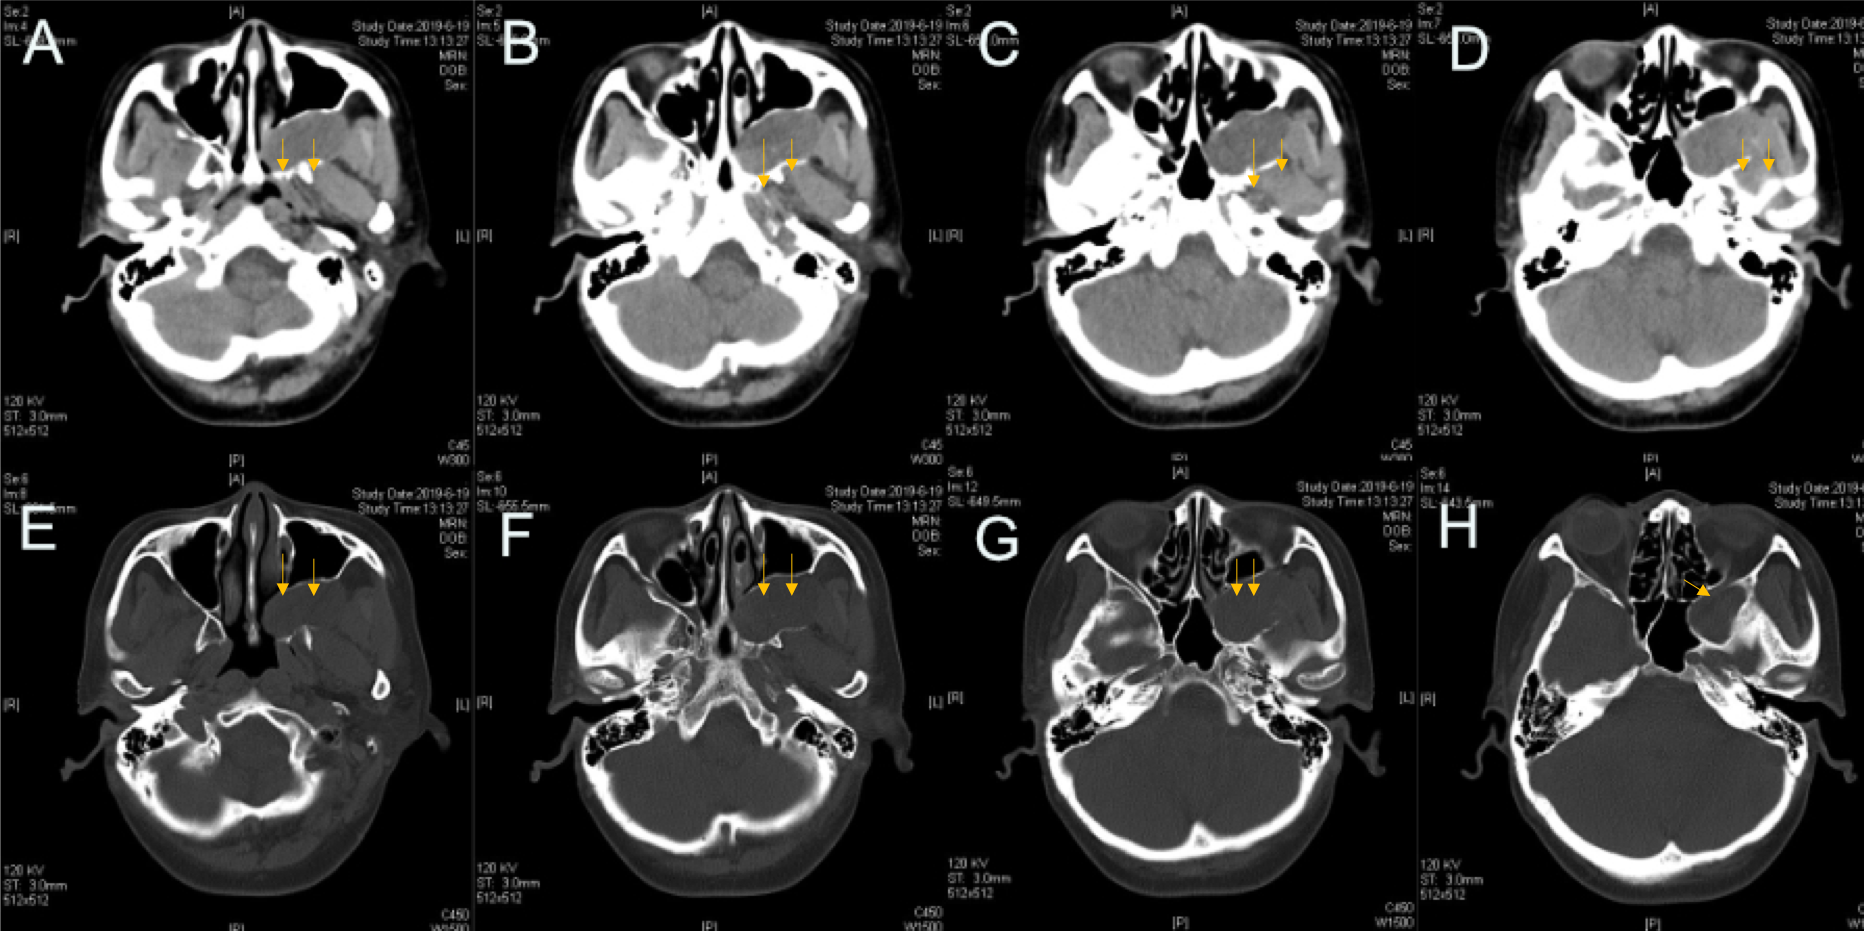

图1.蝶鞍区CT:左侧颅底见梭形软组织密度影,大小约3.7*1.9㎝,周围骨质受压变薄。